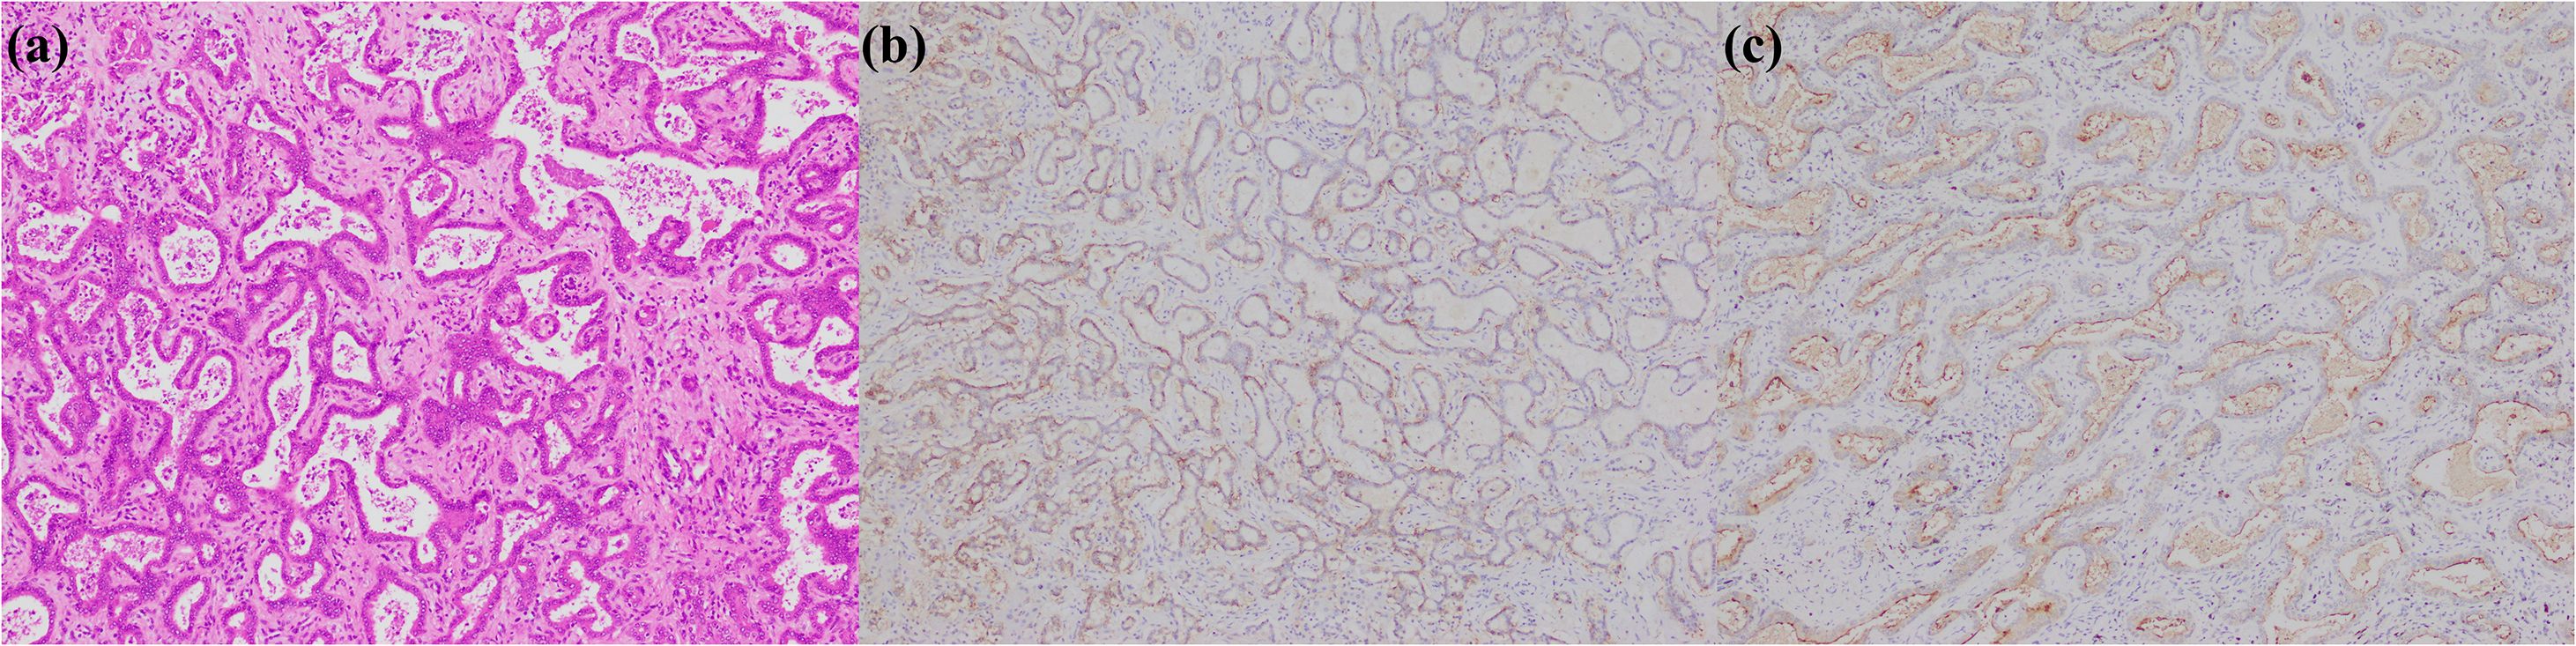

In summary, the expression of immunohistochemical markers in small duct type iCCA is primarily observed in the cytoplasm of tumor cells and shows organ specificity, particularly for CRP and N-cadherin (Figure 2). This enables the application of these markers to extend from subtype diagnosis to differential diagnosis. Furthermore, the liver specifically synthesizes albumin, so albumin in situ hybridization has been increasingly performed for the diagnosis and differential diagnosis of liver tumors in recent years. Numerous studies showed that the percentage of positive cases of albumin in situ hybridization in small duct type iCCA is significantly higher than in large duct type iCCA, and both are higher than in metastatic adenocarcinoma. Consequently, albumin in situ hybridization can serve as a novel method for the histological subtype diagnosis and differential diagnosis of iCCA, supplementing immunohistochemistry (29, 52, 70, 95–98).

Figure 2. Small duct type iCCA. (a) histological morphology; (b) CRP positive; (c) N-cadherin positive; (d) CD56 positive (magnification: 100×).